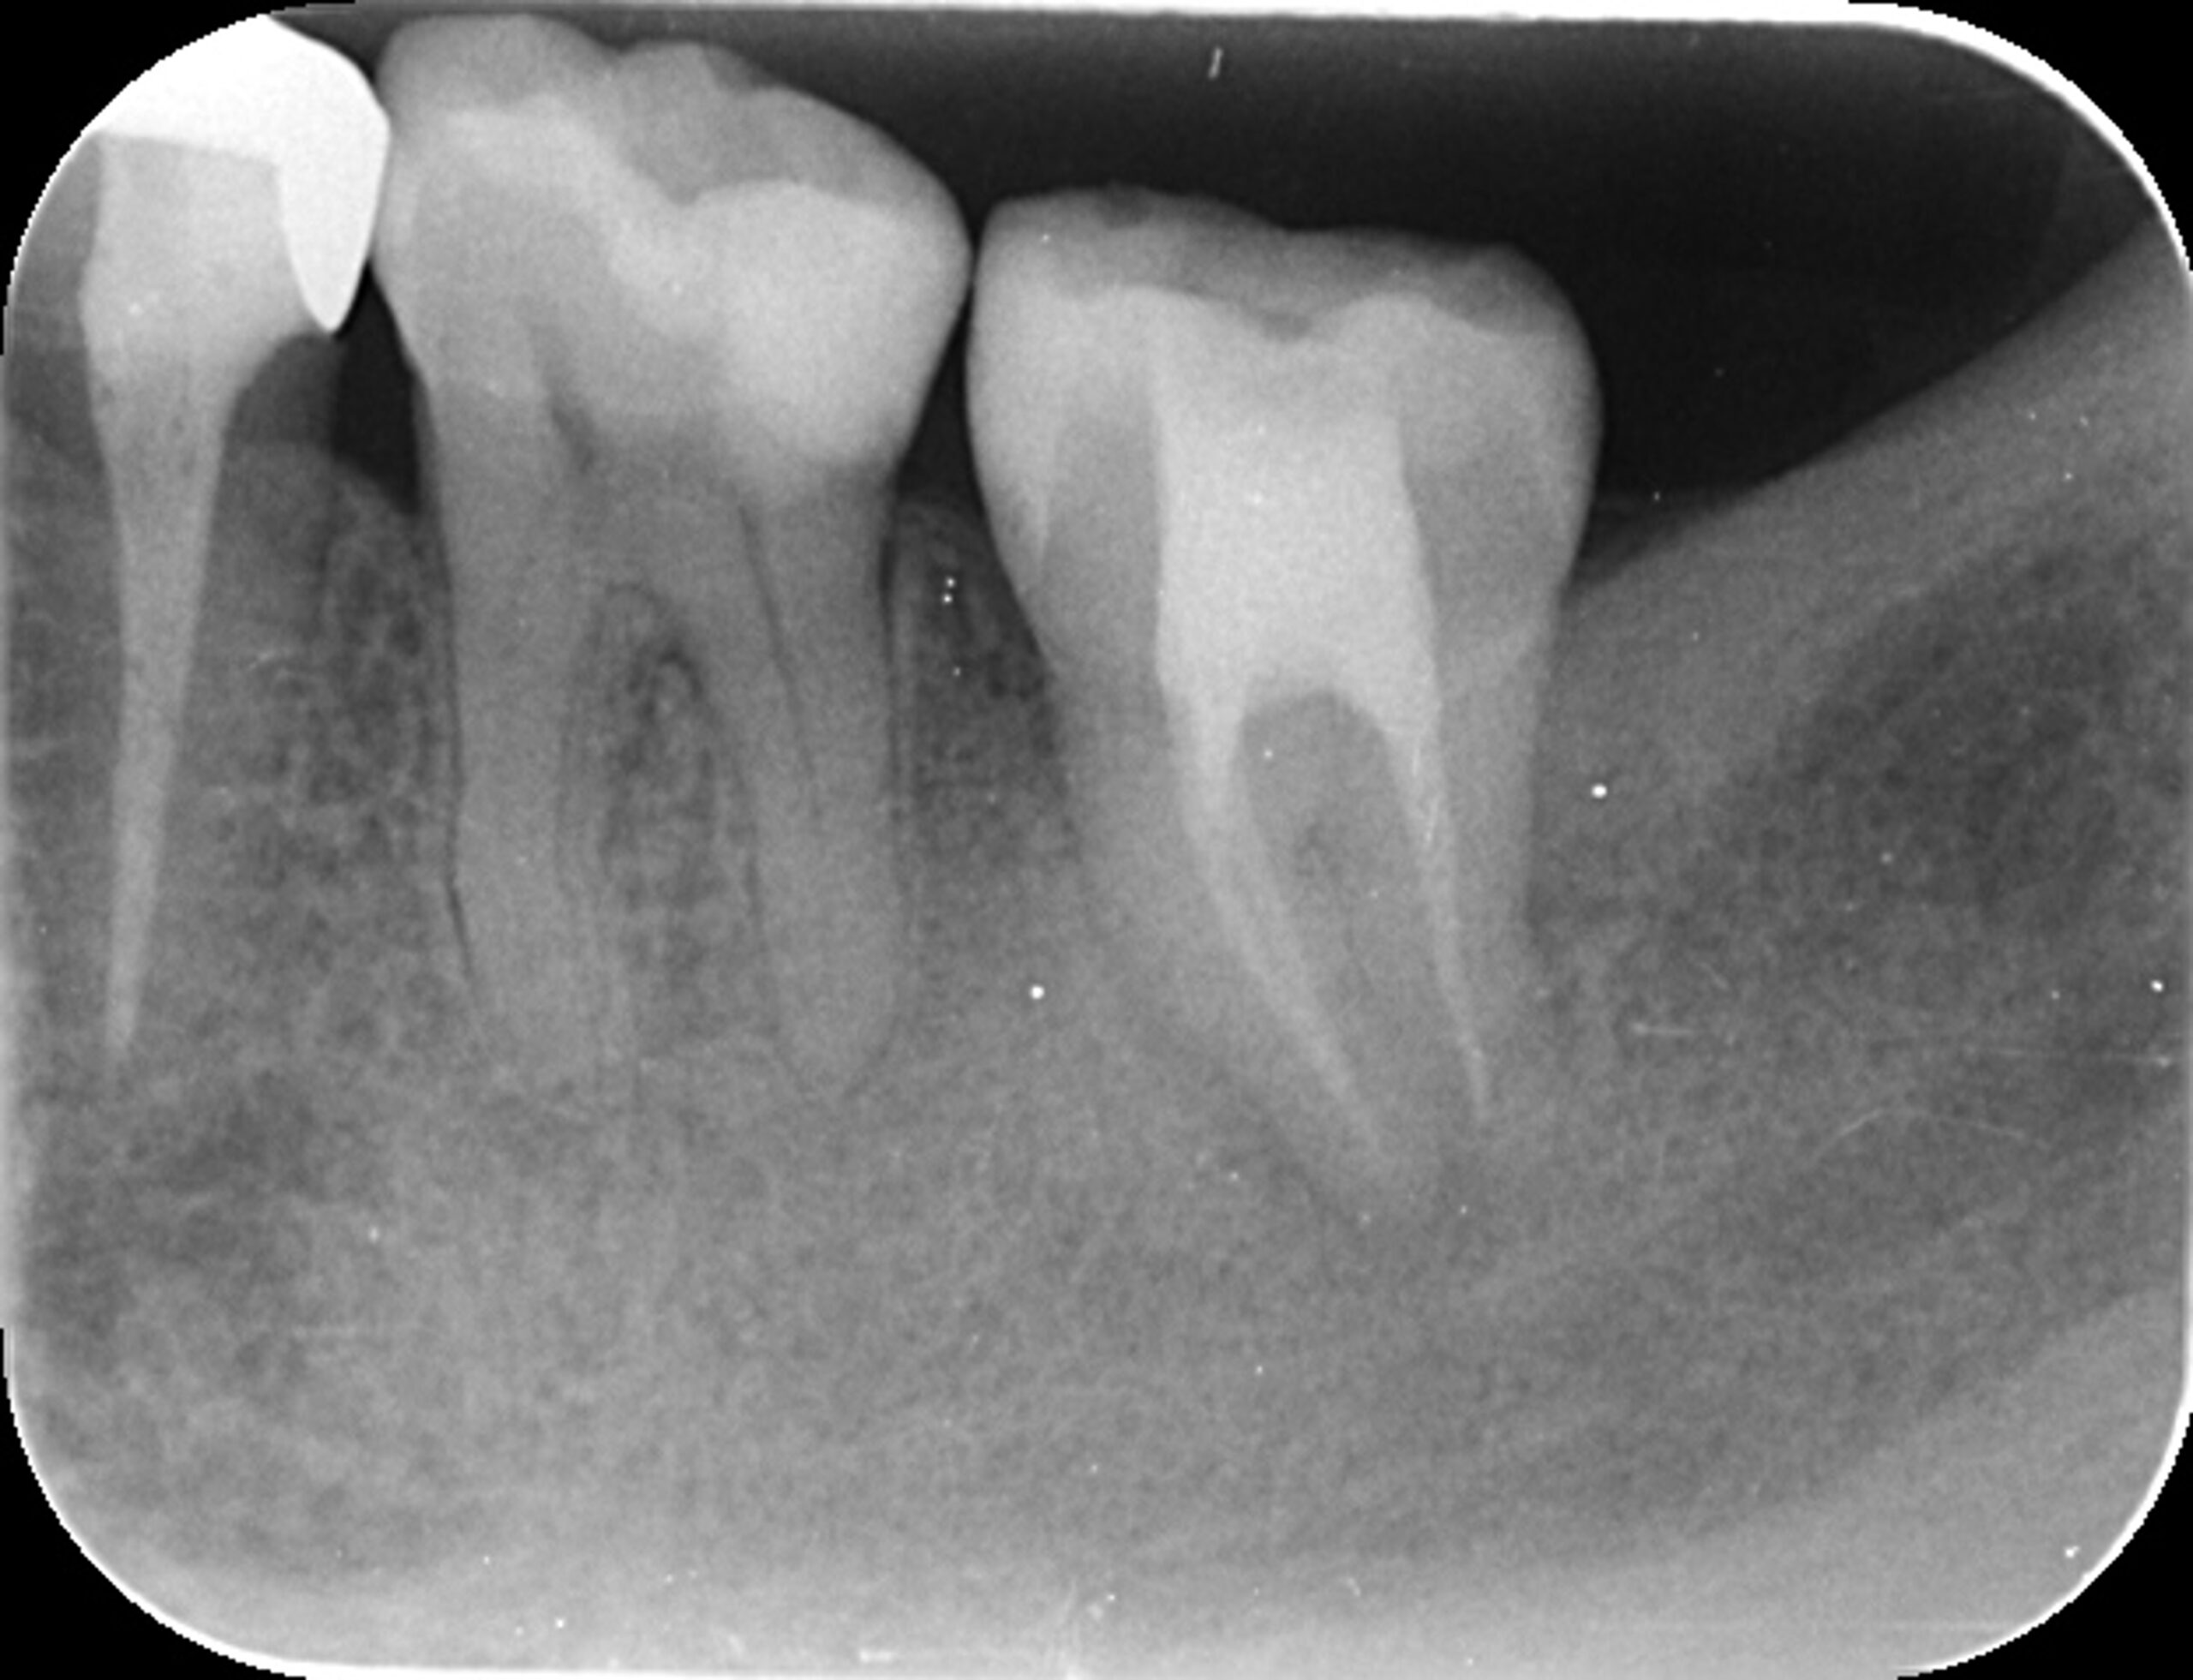

右下親知らずを右下第二大臼歯へ移植

| 患者様データ | 20代 女性 |

| 来院時の主訴 | 「右下奥歯で噛むと痛い。」 |

| 医院の診断 | 歯根破折 |